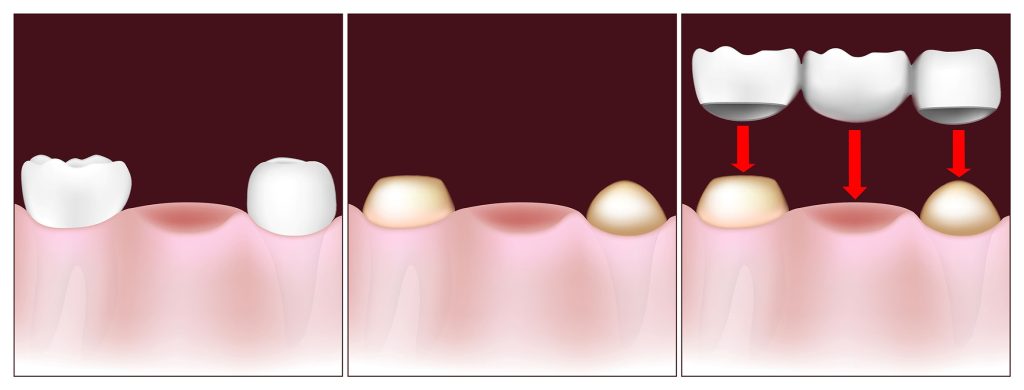

مراحل و نحوه بریج دندان به ترتیب به شرح زیر می باشد:

- در مرحله اول در صورتی که دندان های اطراف فضای خالی، سالم باشد دندان پزشک آن دو دندان را برای قرار دادن روکش آماده می کند اما اگر این دو دندان به منظور حمایت از دندان مصنوعی مناسب نباشد، دندان پزشک مجبور می شود از طریق جراحی، ایمپلنت هایی را درون لثه قرار دهد.

- در مرحله دوم دندان پزشک از دستگاهی برای تشکیل روکش دندان های اطراف فضای خالی و دندان مصنوعی استفاده میکند. به روکش دندان و دندان مصنوعی، بریج گفته می شود.

- در طی مدت زمانی که قالب آماده شود که معمولا 2 هفته طول می کشد، پزشک یک قالب موقتی بر روی دندان های تراشیده و لثه برای جلوگیری از آسیب دیدگی قرار میدهد.

- در مرحله اخر، بریج موقتی برداشته شده، و بریج های تشکیل شده بر روی دندان ها، چسبانده می شود.